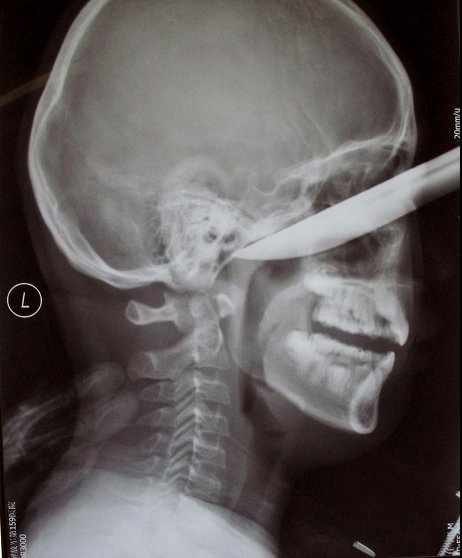

knife

A stunning X-ray image shows a knife stuck deep inside a Chinese teenager's cheek. Ren Hanzhi, 13, tripped and fell while peeling an apple -- jamming himself in the face with a nearly 8-inch knife on Jan. 31. Amazingly, the blade did not strike the boy's brain and doctors were able to remove the knife, expecting him to make a full recovery.